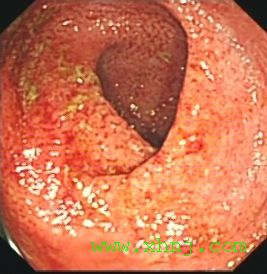

診斷上主要依靠纖維結腸鏡檢,因為約在90%~95%患者直腸和乙狀結腸受累,因此事實上通過纖維乙狀結腸鏡檢已能明確診斷。鏡檢中可看到充血、水腫的黏膜,脆而易出血。在進展性病例中可看到潰瘍,周圍有隆起的肉芽組織和水腫的黏膜,貌似息肉樣,或可稱為假息肉形成。在慢性進展性病例中直腸和乙狀結腸腔可明顯縮小,為明確病變範圍,還是套用纖維結腸鏡作全結腸檢查,同時作多處活組織檢查以便與克隆結腸炎鑑別。

慢性潰瘍性結腸炎 腸鏡表現2、黏膜活檢組織學檢查呈炎症性反應,同時可見糜爛、潰瘍、隱窩膿腫、腺體排列異常、杯狀細胞減少及上皮變化。

重度 慢性潰瘍性結腸炎診斷步驟